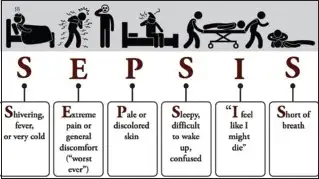

琼斯标准将临床表现分为主要标准和次要标准。主要标准包括:心脏炎、多关节炎、舞蹈病、环形红斑和皮下结节。次要标准包括:发热、关节痛、既往风湿热或风湿性心脏病史、血沉升高或C反应蛋白阳性、心电图PR间期延长。诊断急性风湿热需要存在两个主要标准,或一个主要标准加两个次要标准,加上近期链球菌感染的证据。